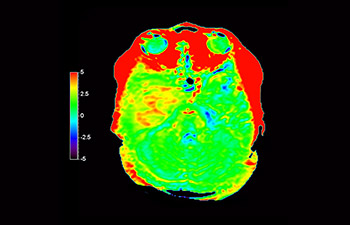

Neurologische Leiden stellen eine schwere Belastung dar. Philips hat es sich zum Ziel gesetzt, hochwertigste Neuro-Bildgebung zu ermöglichen – für eindeutige Diagnosen und eine schnelle Therapie. Wenngleich die MRT heutzutage den Goldstandard in der neuroradiologischen onkologischen Bildgebung darstellt, kann die Genauigkeit beim Tumor-Grading und den Nachsorgeuntersuchungen noch weiter verbessert werden. 3D APT (Amide Proton Transfer) ist eine einzigartige, kontrastmittelfreie Methode zur MR-Tomographie des Gehirns, die den Bedarf nach einer sichereren Diagnose in der Neuroonkologie erfüllt. 3D APT nutzt das Vorhandensein von endogenen zellulären Proteinen zur Erzeugung eines MR-Signals, das direkt mit der Zellproliferation, einem Marker für Tumoraktivität, korreliert. 3D APT kann geschulte medizinische Fachkräfte dabei unterstützen, gering differenzierte von hochdifferenzierten Gliomen und Tumorverhalten von Behandlungseffekt zu unterscheiden1.

mit 3D APT